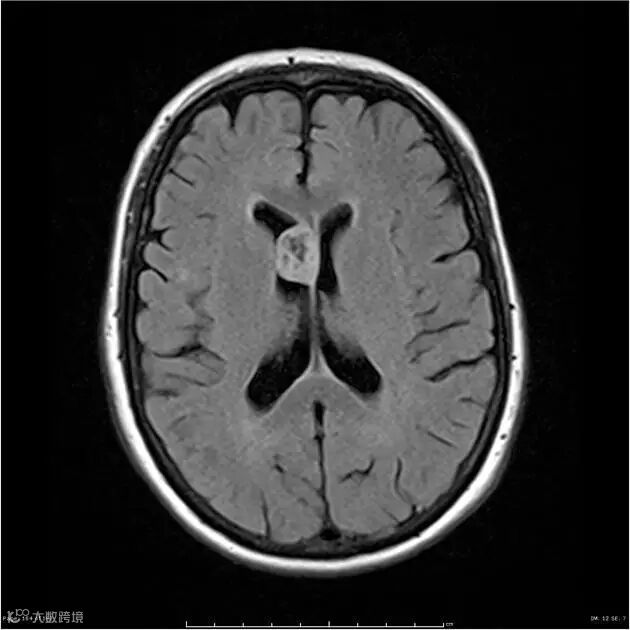

FLAIR